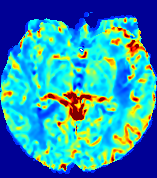

4.3.2 Diffusion Imaging via Advection-Diffusion

Slice #1Slice #2Slice #3Slice #4Slice #5Slice #6Dgtsuperscript𝐷gtD^{\text{gt}}Refer to captionRefer to captionRefer to captionRefer to captionRefer to captionRefer to captionDestsuperscript𝐷estD^{\text{est}}Refer to captionRefer to captionRefer to captionRefer to captionRefer to captionRefer to captionRefer to caption0.300.300.300.240.240.240.180.180.180.120.120.120.060.060.060.000.000.00(mm2/s)𝑚superscript𝑚2𝑠(mm^{2}/s)𝐕est𝟐subscriptnormsuperscript𝐕est2\|\bf{V}^{\text{est}}\|_{2}Refer to captionRefer to captionRefer to captionRefer to captionRefer to captionRefer to captionRefer to caption0.00300.00300.00300.00240.00240.00240.00180.00180.00180.00120.00120.00120.00060.00060.00060.00000.00000.0000(mm/s)𝑚𝑚𝑠(mm/s)

Figure 15: PIANO identifiability testing: diffusion imaging via advection-diffusion. Top row shows Dgtsuperscript𝐷gtD^{\text{gt}} used for simulating ground truth pure diffusion. Rows below show the estimated Destsuperscript𝐷estD^{\text{est}} and 𝐕est2subscriptnormsuperscript𝐕est2\|{\bf{V}}^{\text{est}}\|_{2} on corresponding slices. Note that the plotted value scale for 𝐕est2subscriptnormsuperscript𝐕est2\|{\bf{V}}^{\text{est}}\|_{2} is 0.01 of that for Dgtsuperscript𝐷gtD^{\text{gt}} and Destsuperscript𝐷estD^{\text{est}}.

Similarly, we test the behavior of PIANO when estimating both advection and diffusion from a pure diffusion-driven process. The goal is to determine if PIANO is able to recognize that there is only diffusion governing the given concentration time-series. We use the same ‘Diffusion Imaging’ data simulation of Sec. 4.2.1 as the concentration dataset, PIANO estimates both velocity 𝐕estsuperscript𝐕est{\bf{V}}^{\text{est}} and diffusivity Destsuperscript𝐷estD^{\text{est}}. Estimation results in Fig. 15 confirm PIANO’s identifiability again: the estimated 𝐕est2subscriptnormsuperscript𝐕est2\|{\bf{V}}^{\text{est}}\|_{2} is almost invisible compared to Destsuperscript𝐷estD^{\text{est}}, even plotted with a 1%percent11\% value range compared to that for Destsuperscript𝐷estD^{\text{est}}. On the other hand, Destsuperscript𝐷estD^{\text{est}} achieves comparable estimation performance as ‘Diffusion Imaging via Diffusion’ in which PIANO predicts Destsuperscript𝐷estD^{\text{est}} alone (shown in Fig. 13).